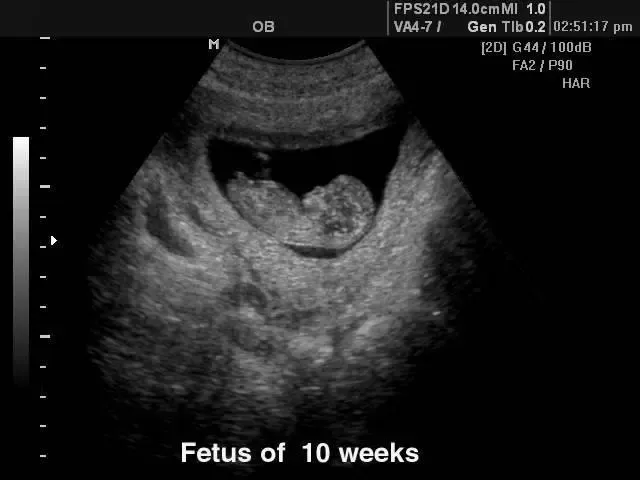

V naši ambulanti se predvsem trudimo, da bi imeli čimbolj profesionalen, diskreten in strokoven pristop k problematiki, ki jo obravnavamo. Da pa bi našim pacientkam zagotovili le najboljše, se nenehno izobražujemo in skušamo dosledno slediti sodobnim smernicam, ki se izoblikujejo tako pri nas kot tudi v tujini. Zato je med drugim na voljo tudi 3d 4D UZ - oziroma ultrazvočni pregled ploda.

V sklopu svoje ambulante ponujamo ginekološko in porodniško dejavnost, poleg tega svojim pacientkam nudimo preglede dojk in različne oblike ultrazvoka. Samoplačniško izdelamo tudi 3D 4D UZ.